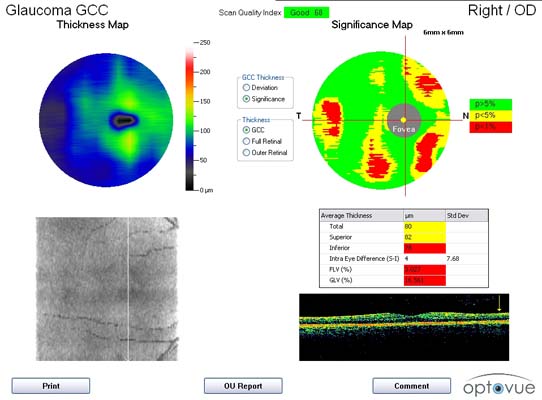

Spektrální optická koherentní tomografie /SOCT/

má výrazně větší přínos než původní optická koherentní tomografie s pomocí „časové domény“ a než GDx.

Na našem pracovišti při diagnostice glaukomu využíváme z nabídky skenů SOCT:

• sken na vrstvu nervových vláken v okolí papily

• měření komplexu gangliových buněk, který se jeví jako citlivější než samotná vrstva nervových vláken

• bezkontaktní měření síly rohovky v průměru 6 mm

Spektrální optická koherentní tomografie /SOCT/ Spektrální optická koherentní tomografie /SOCT/

Přístroj SOCT také umožňuje bezkontaktní zobrazení a měření duhovkorohovkového úhlu,což je možné využít například u dětí, u kterých ještě není možné gonioskopii vyšetřit. Také dokáže zobrazovat 3D tvar papily , který ovšem nedosahuje kvality HRT.

Při diagnostice glaukomu jsou SOCT přístroje podle naší zkušenosti relativně méně senzitivní pro včasný záchyt koncentrického typu glaukomové neuropatie než HRT3! S tímto poznatkem se setkáváme často v naši praxi a není to způsobeno typem SOCT přístroje, ale principem detekce glaukomu metodou SOCT.